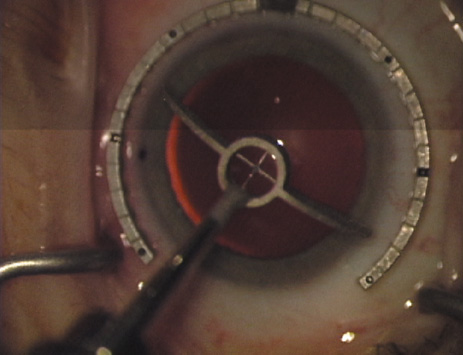

ways. Our preferred method makes use of a modified Fine-Thornton fixation

ring (Nichamin Fixation Ring and Gauge; Mastel Precision, Storz, Rhein

Medical). This instrument serves to fixate and position

the globe in order to optimize incision placement, as well as to delineate

the extent of arc to be incised. One visually extrapolates from

the limbus to marks on the surface of the ring. Each incremental mark

is 10 degrees apart, and bold hash marks (180 degrees) opposite

to each other serve to align and center the incision over the steep

meridian. This approach obviates the need to ink and physically mark

the cornea. If one desires, particularly when first gaining experience

with LRIs, a two-cut RK marker may be used to place ink marks upon the

cornea to show the exact extent of arc that is to be incised, in conjunction

with the fixation ring/gauge (Fig. 4). Alternatively, various press-on markers are available, such as

markers, rings, and blades for performing LRIs.  Fig. 4. The Nichamin Fixation Ring and Gauge serves to both fixate the globe and

delineate the extent of arc to be incised; a two-cut radial marker may

be used to mark the extent of arc to be incised, and the Mastel Nichamin

Force AK Diamond Blade with preset depth of 600 microns. Fig. 4. The Nichamin Fixation Ring and Gauge serves to both fixate the globe and

delineate the extent of arc to be incised; a two-cut radial marker may

be used to mark the extent of arc to be incised, and the Mastel Nichamin

Force AK Diamond Blade with preset depth of 600 microns.